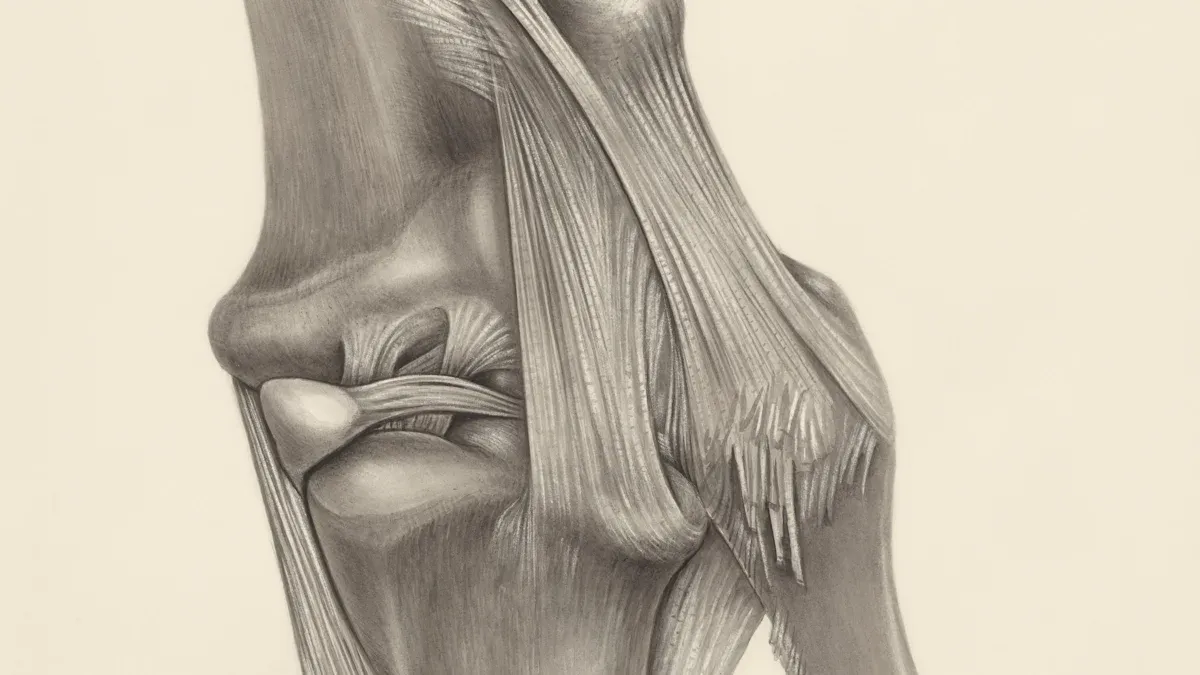

How It Supports Cartilage and Connective Tissue

You want strong joints and lasting mobility. Glucosamine acts as a building block for glycosaminoglycans and proteoglycans, which are vital for cartilage health. Vegetarian glucosamine helps your body synthesize these compounds, supporting cartilage regeneration and joint mobility. Studies show glucosamine supplementation can reverse inflammation in chondrocytes and boost hyaluronic acid production. The table below highlights how vegan glucosamine works:

| Supporting cartilage structure | Maintains joint space and function |

| Reducing inflammation | Eases joint discomfort |

| Improving joint lubrication | Enhances joint mobility |

| Enhancing repair processes | Promotes tissue regeneration |

| Antioxidant protection | Shields joint tissue from damage |